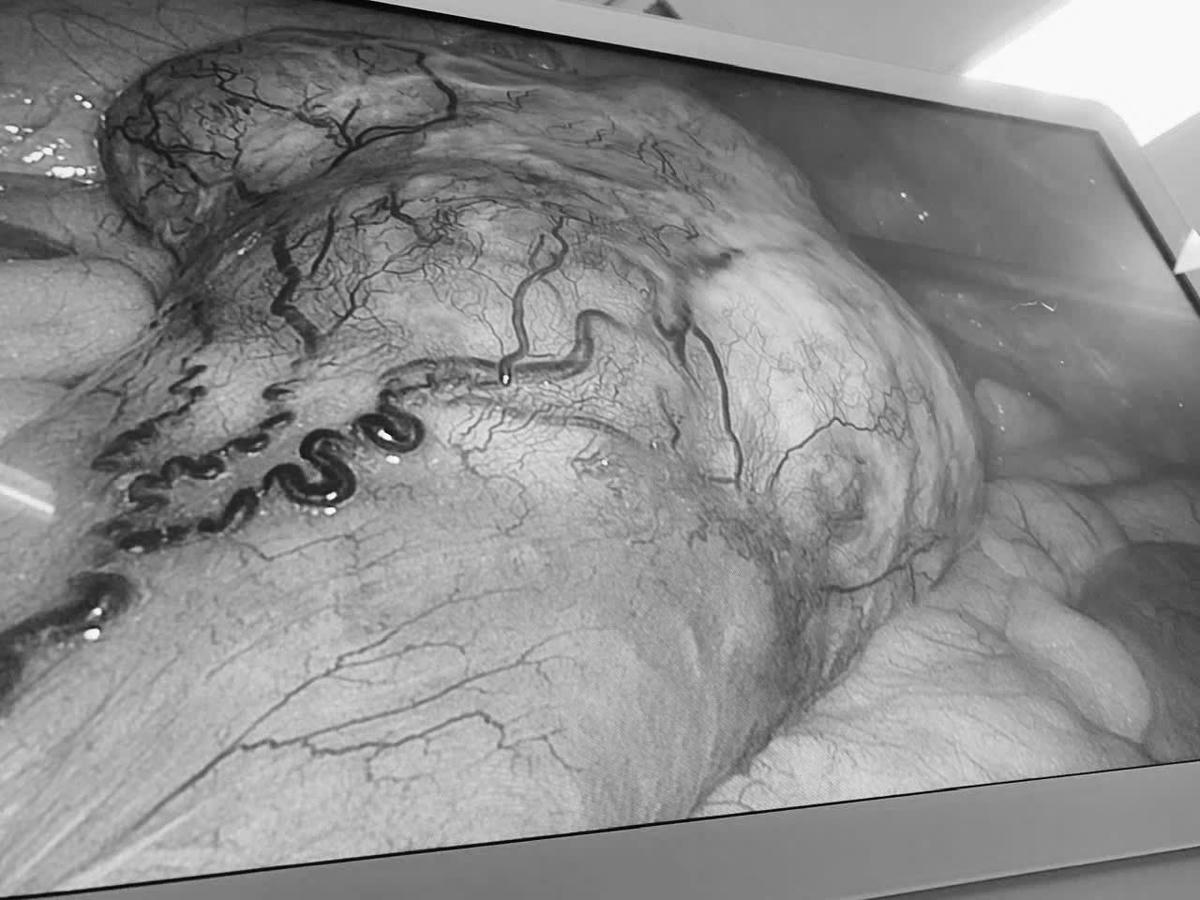

Sau hội chẩn, các bác sĩ Bệnh viện Đa khoa Vĩnh Long thống nhất phẫu thuật cắt bỏ đồng thời hai khối u bằng phương pháp nội soi nhằm giảm xâm lấn và rút ngắn thời gian hồi phục.

Ca mổ kéo dài 180 phút, hai khối u được lấy trọn, đảm bảo nguyên tắc ung thư học, không phải chuyển sang phẫu thuật mở, lượng máu mất khoảng 100 ml.